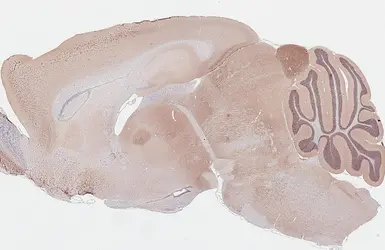

GABA A Receptor alpha 1 antibody [GT154] detects GABA A Receptor alpha 1 protein by immunohistochemical analysis.

Sample: Paraffin-embedded mouse brain.

GABA A Receptor alpha 1 stained by GABA A Receptor alpha 1 antibody [GT154] (GTX642581) diluted at 1:50.

Antigen Retrieval: Tris-EDTA buffer, pH 9.0, 15 min